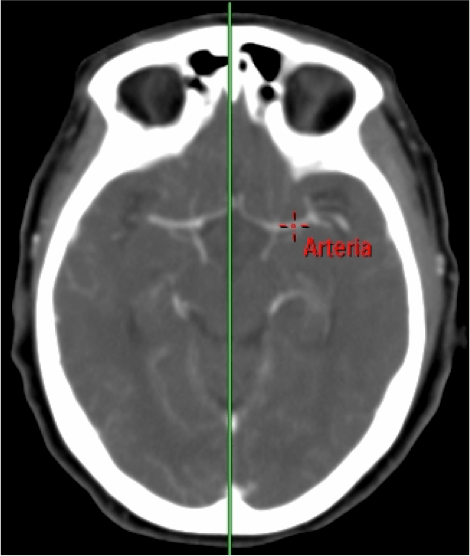

El fundamento de la prueba consiste en administrar constraste iv y estudiar el primer paso de éste a través de la circulación cerebral (50 mL de cc; 4 mL/seg) a baja radiación (80 kVp; 150 mA). Se realiza un bloque de estudio de 4 cm a nivel de los ganglios basales (ya que a ese nivel encontramos los territorios de las ACA, ACM y ACP) y se aprovecha que el contraste pasa a través de la circulación cerebral produciendo hiperatenuación de los vasos, lo cual vamos a aprovechar para colocar un ROI arterial y otro ROI venoso que nos darán dos curvas de tiempo-atenuación de contraste

PASO 1º: COLOCAR LA LINEA MEDIA.

PASO 2º: DEFINIR VASOS. Colocación de los ROI.

- El ROI arterial debe seleccionarse en un arteria sana, preferiblemente en las ACA o en la ACM contralateral al lado infartado.

- El ROI venoso puede aplicarse por ejemplo en el seno venoso sagital superior o en la prensa de Herófilo.